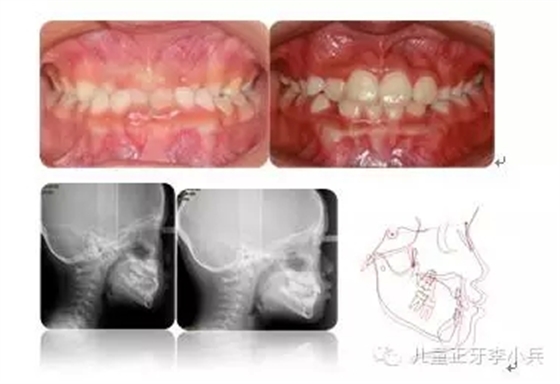

4.III類骨性畸形的早期矯治:傳統(tǒng)的功能矯形概念是在兒童青春發(fā)育高峰前期開始。對于骨性III類的矯形治療的開始時間,國內(nèi)外一直存在爭議。華西兒童早期矯治專科在總結本科III類骨性矯治的療效后,認為III類骨性的矯形矯治在第一橫磨牙萌出時(6歲)開始必在青春發(fā)育高峰前期(9歲)時開始能得到更多的骨性改變。(圖5,III類骨性的早期功能矯形治療)必須強調(diào)的是,早期功能矯形治療必須保持到恒牙列初期(12歲)以維持矯形治療的效果,避免由于遺傳的影響造成的矯形治療的復發(fā)。

圖 5 骨性III類錯合的早期矯治,保持持續(xù)到兒童發(fā)育結束;